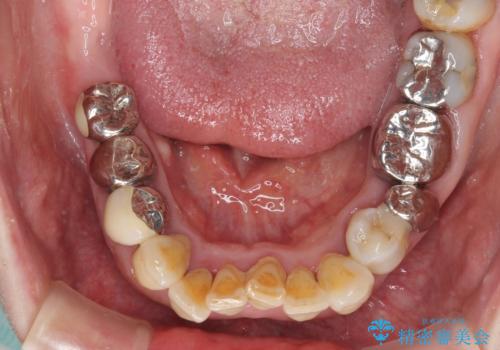

- 歯茎からの出血、入れ歯、歯の欠損、デコボコの前歯などを気にして来院された患者様です。

大の歯科治療嫌いとのことでしたが、今回の治療を契機にしっかりと治療を行いたいとのことでした。

まずは抜歯が必要な歯を抜歯した上で仮歯に置き換え、インプラント埋入や歯周外科処置、根管治療を行うこととしました。

歯肉の状態が落ち着いた後に下顎の矯正治療を行い、その後補綴治療を行うこととしました。